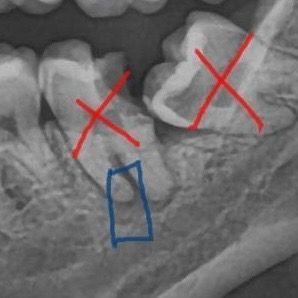

원래 사랑니 앞에 이라서 양치가 잘 안됐는데 치과 공포증 때문에 미루다보니까 엄청 상해서 밥 먹다가 이가 깨졌어요 ㅠㅠㅠ 처음엔 치과가서 신경치료만 하고 크라운 씌우면 되겠다 싶었는데 의사 분께서 보더니 임플란트 해야할 것 같다고 하시더라구요… ㅠㅠ 근데 제가 잇몸뼈? 아무튼 그게 짧아서 뼈 이식을 해야할 것 같대요. 근데 뼈 이식 하고 1년 정도 기다려서 뼈 차오르는걸 보고 만약 뼈가 차오르면 임플란트를 하고 아니면 위에 치아가 놀아서 자꾸 내려올테니 그냥 이 없이 살아야할 것 같다 하시더라구요..? 이런 경우가 흔치 않은 것 같은데 제가 정말 임플란트도 부족한 정도인가요..? 양악수술 이런것도 한적 없고 그냥 20대인데 혹시 덤티기 당한건 아닌가 싶어서 여쭤보ㅓ요ㅠㅠ!!

말씀하신 치아는 치아 뿌리의 염증이 많아 보입니다. 염증이 있다고 해서 임플란트가 불가능한 것은 아니나 말씀하신 치아는 뿌리 하방에 신경이 지나가므로 임플란트 식립이 바로 불가능합니다. 이러한 경우에는 뼈이식을 하거나 뼈를 충분히 회복 시킨 다음에 재평가를 해야 합니다. 만약에 뼈이식 등을 하더라도 신경과 거리가 너무 가깝다면 임플란트 식립 자체가 불가능할 수 있습니다.

GI 프리 끝이 신경관과 가까워 보입니다. 이런 경우 임플란트를 하게 되면 신경관에 손상이 가해질 수 있습니다. 따라서 우선 골이식을 해서 뼈를 만든 후 임플란트를 고려해 보는 것이 좋을 것으로 생각됩니다.

치아 바로 밑쪽으로 신경이 지나가고 있는 형태의 구조이므로 뼈이식 후 임플란트 하시면 됩니다.

저정도 치아 상태라면 발치를 해야될것같습니다. 치아 밑으로 염증이 심해서 뼈이식도 필요해 보입니다.

사랑니때문에 그 앞 어금니가 썩고, 깨졌으며 뿌리에 염증이 있습니다 사랑니랑 그 앞 어금니 빼야하고요 임플란트 심기 전 뼈이식 더 해주면 좋을 것 같습니다

위 어금니 내려오지 않게 방치하지 말고 와이어로 고정시켜서 조치를 취해주는게 좋겠죠